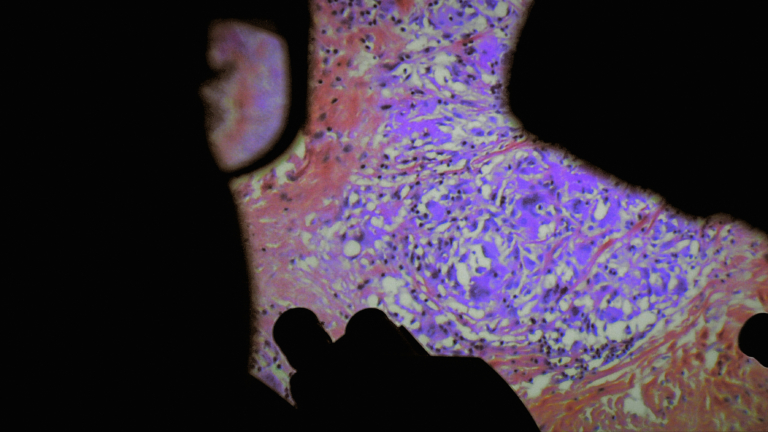

De Humani Corporis Fabrica

France - 2022 - 1H55

Il y a cinq siècles l’anatomiste André Vésale ouvrait pour la première fois le corps au regard de la science. DE HUMANI CORPORIS FABRICA ouvre aujourd’hui le corps au cinéma. On y découvre que la chair humaine est un paysage inouï qui n’existe que grâce aux regards et aux attentions des autres. Les hôpitaux, lieux de soin et de souffrance, sont des laboratoires qui relient tous les corps du monde…

Voir les séances

Le Monde : « Fait de collages d’images médicales, le documentaire de Verena Paravel et Lucien Castaing-Taylor (LEVIATHAN – 2013) ouvre des perspectives esthétiques et anthropologiques. Le corps humain palpite sous les caméras endoscopiques infiltrant ses innombrables « tuyaux » intérieurs, à la recherche d’une excroissance ou d’une cellule à éliminer. Nous voici dans les « cuisines » de l’hôpital public, au cœur de différents blocs opératoires, où les deux anthropologues ont été autorisés à filmer, ainsi qu’à télécharger l’imagerie médicale des interventions. En allant dans les « sous-sols », les réalisateurs livrent incontestablement un festin d’images, dont certaines sont propices au fantasme, à l’onirisme, même si le rêve est parfois interrompu par le bruit agressif de divers appareils médicaux (sondes, aspirateurs). Dans ces moments-là, le spectateur aura plutôt tendance à s’agripper au fauteuil comme dans un train fantôme.«